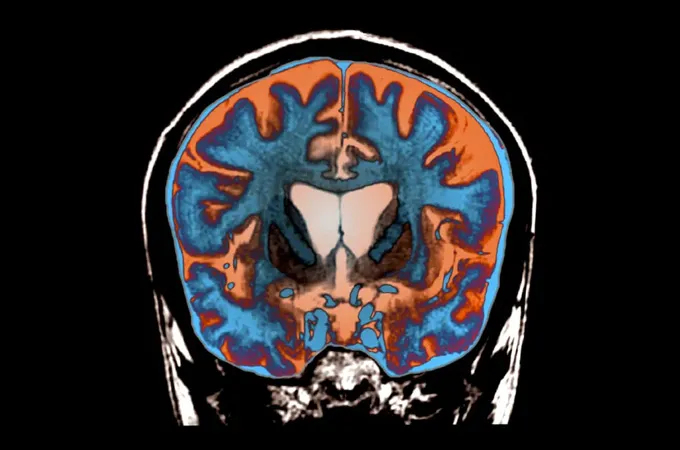

Впервые замедление роста Хантингтона

Это мозг человека с болезнью Хантингтона. Желудочки — открытые полости для циркуляции спинномозговой жидкости — расположены в центре и намного больше, чем обычно, что свидетельствует о дегенерации близлежащих областей мозга.Zephyr/Научный источник

Болезнь Хантингтона — это прогрессирующее неврологическое заболевание, которое лишает людей контроля над своим телом. Пациенты могут замирать, непроизвольно дергаться или корчиться. У врачей нет эффективных методов лечения, но экспериментальный препарат может изменить ситуацию. Препарат состоит из вируса, содержащего крошечные фрагменты РНК, которые останавливают выработку болезнетворных белков. Введенный в мозг препарат замедлил прогресс в развитии Хантингтона на 75 процентов — триумф ученых и многообещающий знак для пациентов.